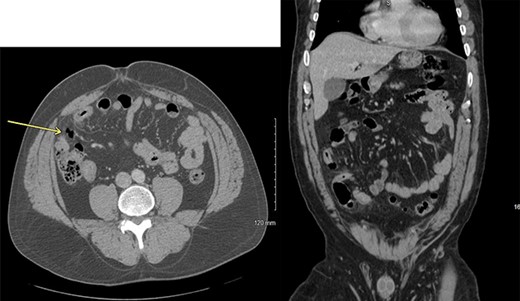

He presented to the emergency room with worsening lower abdominal pain for 1 week after undergoing bilateral ilioinguinal and iliohypogastric hot RF ablation with Pain Management. Per outside hospital, he underwent RF ablation at 80°Cfor 90 s. Computed tomography imaging was obtained which showed an inflamed area of small bowel with a localized area of pneumoperitoneum (Fig. 1). Given his normal vitals, lack of peritoneal findings on abdominal exam, and leukocytosis 14 000 with otherwise unremarkable lab work, we elected to initially treat with IV antibiotics, bowel rest and serial abdominal exams. On hospital Day 3, he was taken to the operating room for persistent pain and failure to improve. A diagnostic laparoscopy was performed. There was a scarred area on the peritoneum with adherent small bowel and omentum found. This single adhesion was taken down and the involved jejunal segment was inspected revealing a full-thickness perforation with surrounding erythematous bowel (Fig. 2). The intraoperative findings and timing post-RF ablation were consistent with delayed perforation secondary to jejunal thermal injury. A laparoscopic small bowel resection with intracorporeal stapled anastomosis was performed. His postoperative course was uneventful, and he was ultimately discharged post-op Day 3 after tolerating a diet and having bowel function.

Axial and coronal computed tomography scan views of the patient showing small area of pneumoperitoneum with surrounding small bowel inflammatory changes.